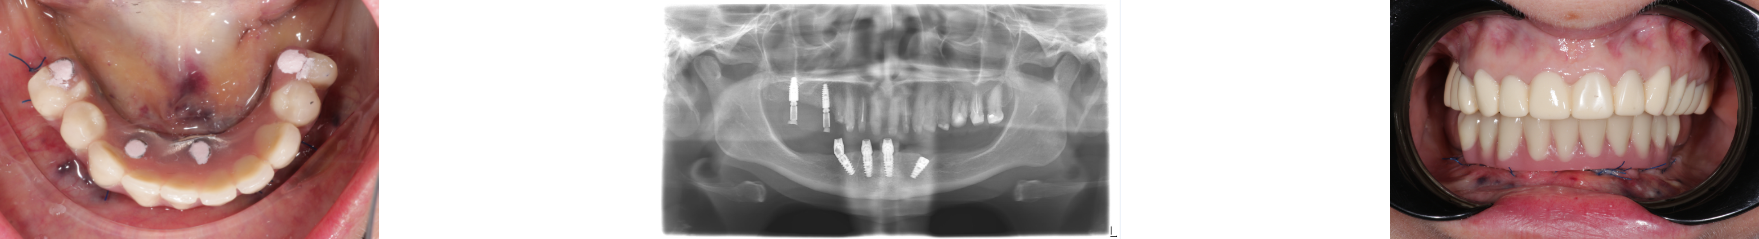

Пациент А

Резюмируя вышесказанное,

методика All-on-4 позволяет получить быстрый

результат протезирования, отказаться

от костной пластики и получить конструкцию

с высоким показателем стабильности.

Лечение пациента по

методике All-on-4 проводится врачом

стоматологом ортопедом и врачом хирургом.

В результате лечения

с применением методики All-on-4 пациент

получает восстановление функции жевания

и эстетики.